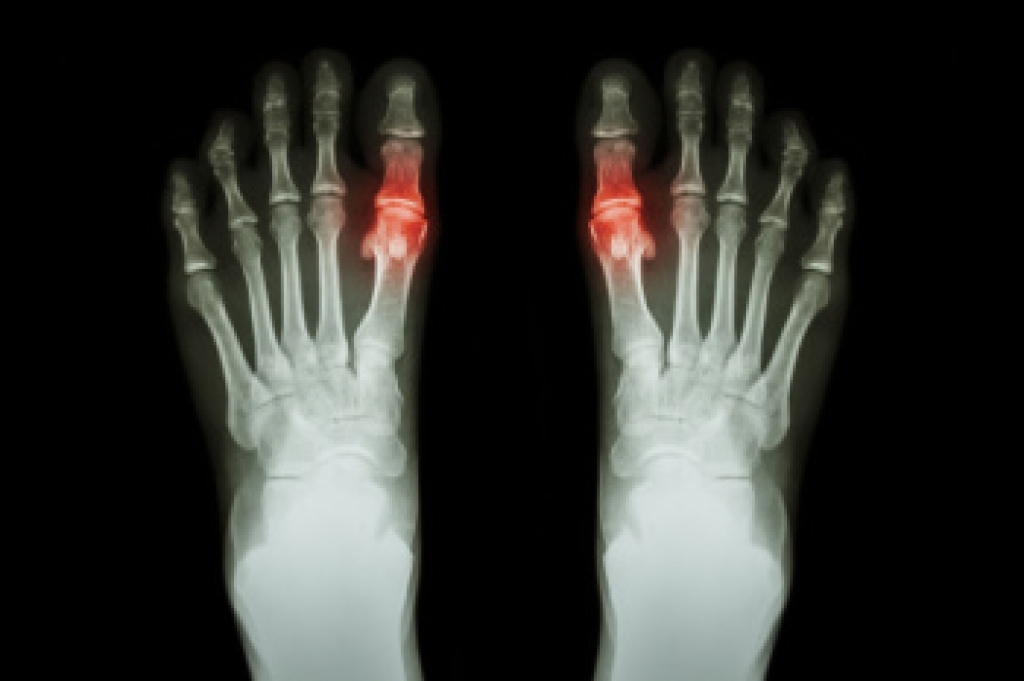

- Bunions

- Arthritis (such as Gout, Rheumatoid, and Osteoarthritis)

To figure out the cause of foot pain, podiatrists utilize several different methods. This can range from simple visual inspections and sensation tests to X-rays and MRI scans. Prior medical history, family medical history, and any recent physical traumatic events will all be taken into consideration for a proper diagnosis.